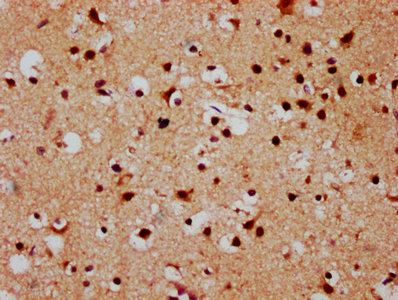

IHC image of CSB-PA861136LA01HU diluted at 1:500 and staining in paraffin-embedded human brain tissue performed on a Leica BondTM system. After dewaxing and hydration, antigen retrieval was mediated by high pressure in a citrate buffer (pH 6.0). Section was blocked with 10% normal goat serum 30min at RT. Then primary antibody (1% BSA) was incubated at 4°C overnight. The primary is detected by a biotinylated secondary antibody and visualized using an HRP conjugated SP system.